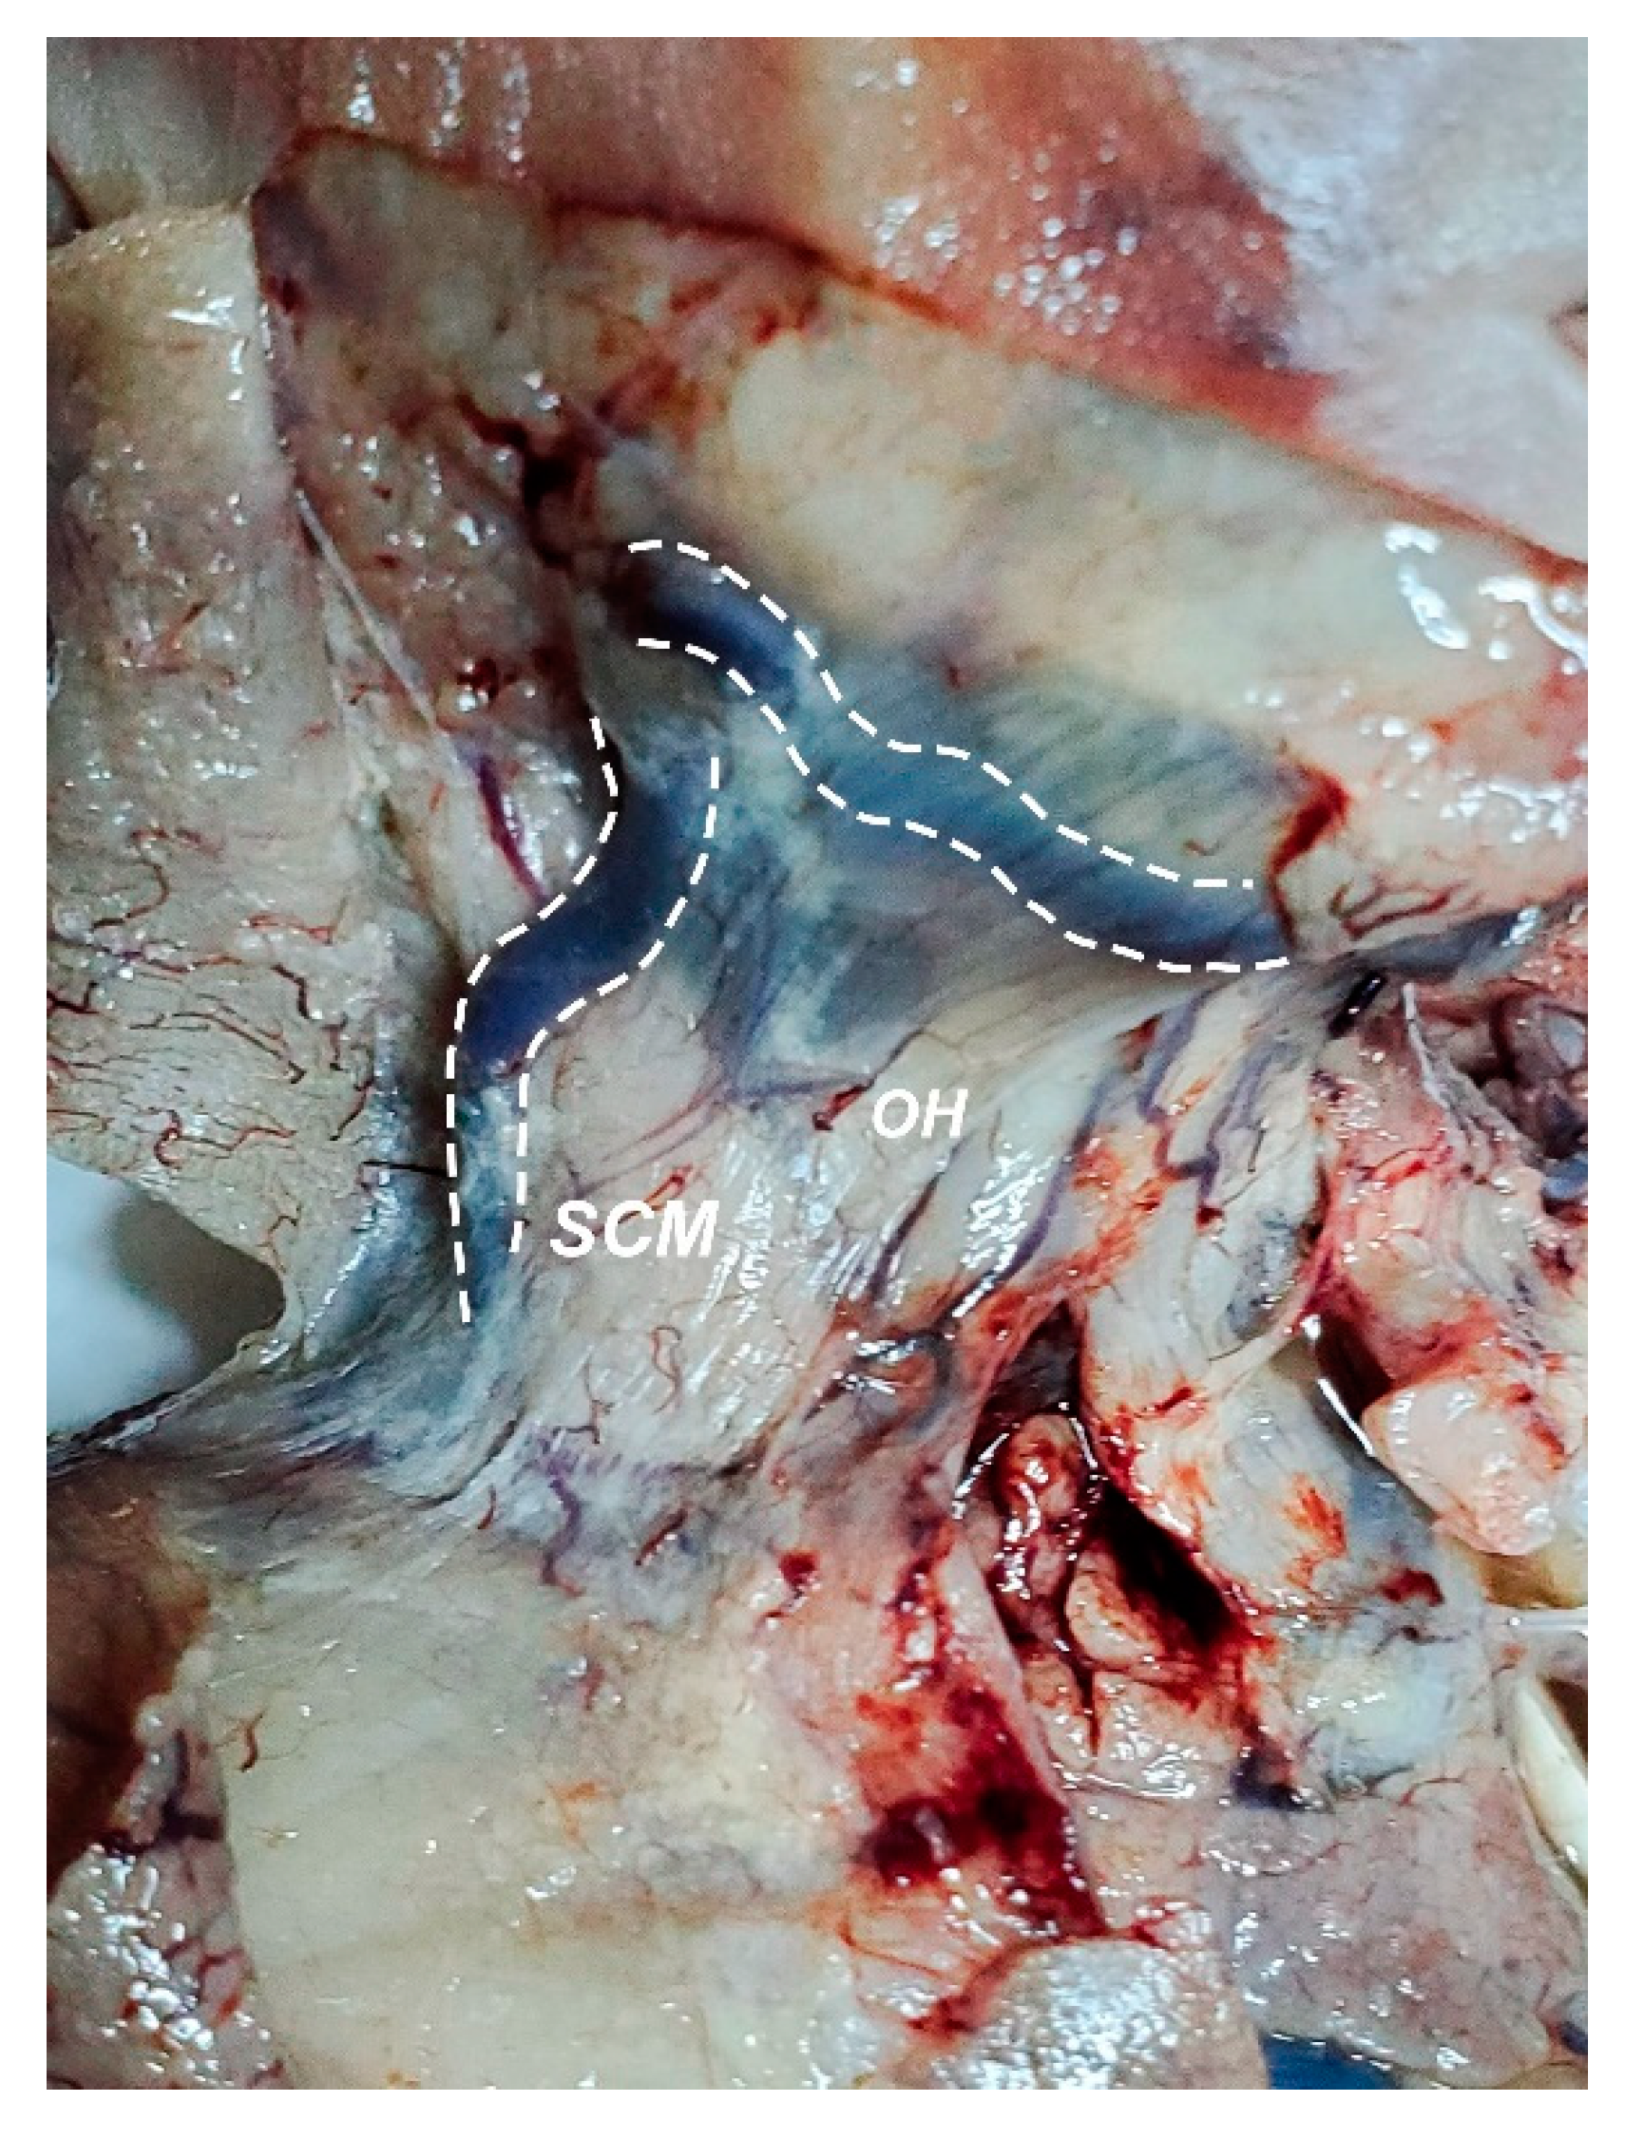

2.2. Dissection